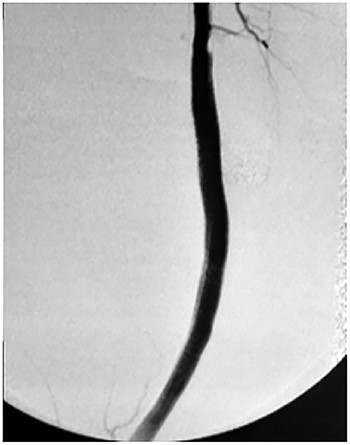

Approval for retrospective reports is not required by our institutional review board. This study is in accordance with the principles of the Declaration of Helsinki. A 77-year-old man with multiple comorbidities, including coronary vascular disease, hypertension, dyslipidemia, previous right carotid endarterectomy, and endovascular aortic repair (in 2011), was referred to our unit for evaluation of a retropopliteal pulsatile mass. He had undergone infra-popliteal stenting 18 months earlier, to treat peripheral arterial disease with severe left claudication. The procedure was performed at another vascular institute, and the stent type was unknown. Physical examination revealed the presence of a femoral and popliteal pulse and the absence of tibial pulses; at admission, the ankle–brachial index was 0.8. According to the patient, he had noticed the mass in the last 2 months prior to admission, but the absence of pain delayed his presentation to the hospital. An ultrasound scan was performed on admission and revealed a large popliteal pseudoaneurysm with normal flow present distally, and fracture of the stent was confirmed by computed tomography, which also detected a 4.2 cm dilatation of the left popliteal artery (Figs 1–3).

Angiotomography showing a fractured stent and pseudoaneurysm at the site of the fracture.

Based on the characteristics of the pseudoaneurysm, we decided on a minimally invasive interventional approach. This was in agreement with other vascular surgeons and the family. Under local anesthesia, the left common femoral artery was punctured in antegrade fashion, and an 8-F sheath was deployed. An X-ray of the popliteal region highlighted the stent fracture, and digital arteriography showed the large pseudoaneurysm. After administration of 5000 IU of heparin, a 0.035 guidewire was passed across the fractured stent and was placed distally in the posterior tibial artery. At the end of the procedure, a 7.0 × 150-mm self-expandable Viabahn endoprosthesis (W. L. Gore & Associates, Flagstaff, AZ, USA) was delivered into the stent, and adjuvant balloon inflation was performed with a 6.0 × 80-mm balloon leading to a complete exclusion of the pseudoaneurysm (Fig. 4). The final angiogram showed no residual stenosis, complete exclusion of the pseudoaneurysm, and no compromise of distal runoff. There were no complications associated with the procedure.